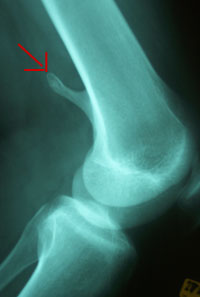

About a year ago, I felt something funny in my left leg. After a couple of runs - Eugene's 10K Butte-to-butte - and other exercises, I started feeling more pain. The pain became more real about 5-6 months ago, so I went to see my doctor. After a couple of X-rays, he said there is a bone growth and he referred me to an orthopedic.

• June 17th 2004 I will have a surgery, "Excision of Osteochondroma Left Femur". It is only a day-surgery and I will not use my leg for a week and thereafter I will be on the crutches I think for few days -- more on this